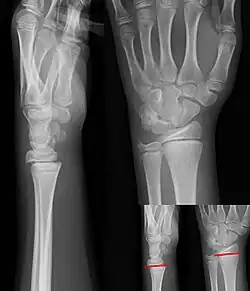

-

Salter–Harris I fracture of distal radius. -

Salter–Harris II fracture of ring finger proximal phalanx. -